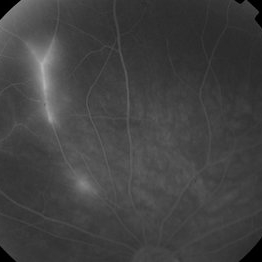

Background: 46-year-old WF with CML (stable on Sprycel) saw her PCP for headaches without known cause; Headaches worsened and became confused, disoriented, off balance, and impaired short term memory. Heme-oncology ordered MRI that showed abnormal signal in the cerebellum and other parts of the brain, and LP has elevated protein. LP did show positive tau test, but fortunately, was a false positive for CJD. IV and PO steroids started and symptoms improved. MRI showed much improvement one month since starting steroids. 3 weeks later had a scotoma in right eye and eye doctor did not find anything at that time to cause it. Tinnitus developed (and some intermittent vertigo before that) and ENT referred back to eye doctor, who then referred the patient to Dr. Zocchi. He found a CWS and BRAO OD, and bilateral arteritis. She had some additional work-up for vasculitis. Given the retinal arteritis, cochlear issues, and MRI findings, Dr.Zocchi suspected Susac's Syndrome. She was started on multiple regimens including prednisone, IVIG, azathiprine, and MTX, and has had the best reponse to IVIG (FA shows a recurrence/worsening while adjusting IMT). She is stable and doing well with 20/20 vision in both eyes.

Photographer: Kay Dalby

Imaging device: Topcon

Condition/keywords: retinal vasculitis, Susac's syndrome